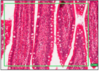

TONGUE - SEROUS GLANDS

- more pink staining (darker than mucous)

- small serous salivary glands

- acini - clusters of grapes

- nucleus on base

MUCOUS GLANDS

- small salivary mucus gland

- michael palin = mucus pale*

mucus glands stain paler than serous!